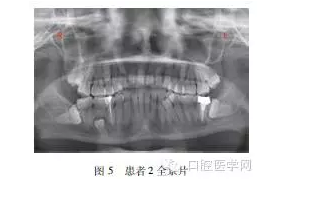

患者2,女,23歲,無遺傳史,母親孕期無特殊接觸史。??茩z查:恒牙28顆,牙列擁擠,4舌側(cè)可見1顆多生牙,形態(tài)大小似前磨牙,57可見充填物。全景片(圖5)示患者88垂直阻生,88近中阻生,45間可見一多生牙近中傾斜萌出,55根方可見一埋伏阻生多生牙,6根方可見一含牙囊腫,內(nèi)含埋伏阻生多生牙牙冠。

治療計(jì)劃:分次拔除下頜2顆多生牙,上頜2顆多生牙因無臨床癥狀,可暫觀察。